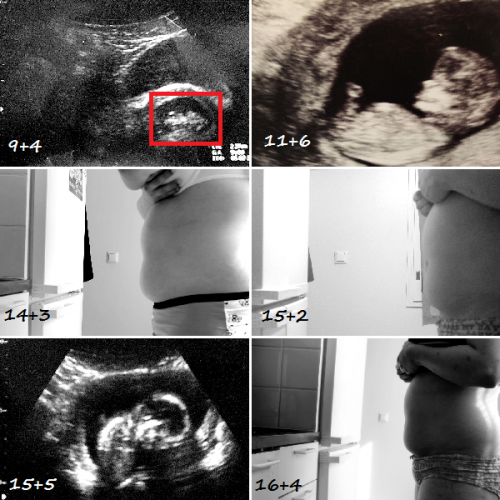

Heipä hei! Tänään siis meni rikki raskauden puoliväli, huisia! 🙂 Maha ei tunnu erityisemmin kasvavan, töissäki sain tällä viikolla kerrottua pomolle että ootan vauvaa, ja seki ihmetteli että oon jo näin pitkällä eikä musta huomaa kyllä yhtään että ootan… Noh, se varmaan pullistuu sitte yhtäkkiä hirviällä rytinällä. 😀 Potkuja, tai mitä lie liikkeitä on alkanu …

Heipä hei! En oo taas kerenny tässä lähipäivinä kirjotella ku on ollu kiireitä. Muuttoa ja sen sellasta… 🙂 Ihanaa, asun nyt tilavassa kaksiossa avoliitossa Juhon kans, huih! 😀 Muutto on saatu nyt kokonaisuudessaan hoidettua ja asiat näyttäs muutenki olevan aika hyvin reilassa. Vauvan odotus on taas huipussaan; tunnen nimittäin mahassa jo jonkimoista liikettä, ja vahvasti …

Iiih, enää en malta olla kertomatta tätä! Mulle tulee vauva! 🙂 Uskallan siitä täällä jo hehkuttaa, ku aika moni läheinen jo tietää tän, eikä tätä blogia juuri kukaan muutenkaan lue. Elikkäs tänään on viikkoja 17+0. Oon tosi tosi innoissani ja oottelen jo kovasti että massu alkais kasvaan. Joka viikko otan kuvan ja yritän kattoo että …